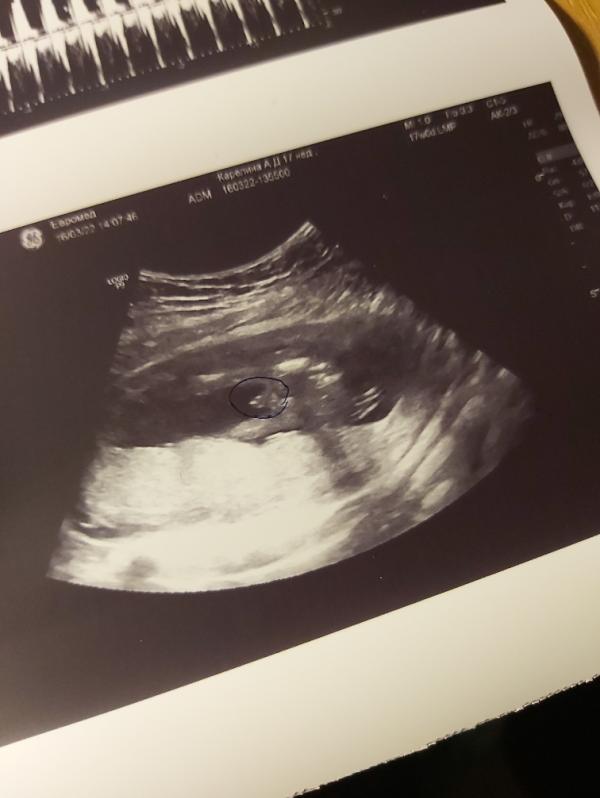

Вчера нам было ровно 17 недель,решила не ждать планового скрининга (он у нас 29.03),и пошла я платно,посмотрели все важные моменты,и нам сказали что у нас мальчик 100%, сделали снимок его сюрприза. Теперь надеюсь 29.03 мне не скажут что у меня девочка,и меня никто не будет путать. И все таки надеюсь что там живет Арсений 😻👶🏻